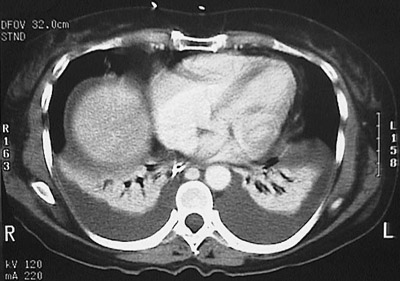

The chest CT scan above demonstrates a bilateral posterior pleural effusions in a patient with congestive heart failure. The fluid layers posteriorly in this patient who is lying down during the CT procedure.